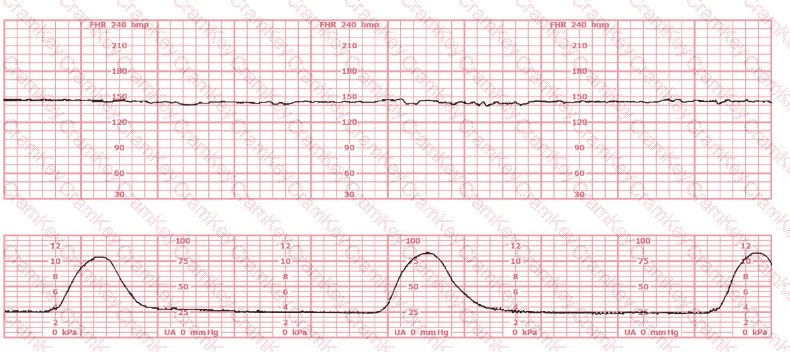

Question 10

A patient at 41 weeks gestation is being induced. She has progressed slowly and is now at 6 cm, 90% effaced, –1 station. She has the fetal heart tracing shown despite repositioning. The next step in the management of this patient should be to:

Questions 10

Options:

A.

Apply a spiral electrode

B.

Decrease the oxytocin

C.

Perform an amnioinfusion

Discussion